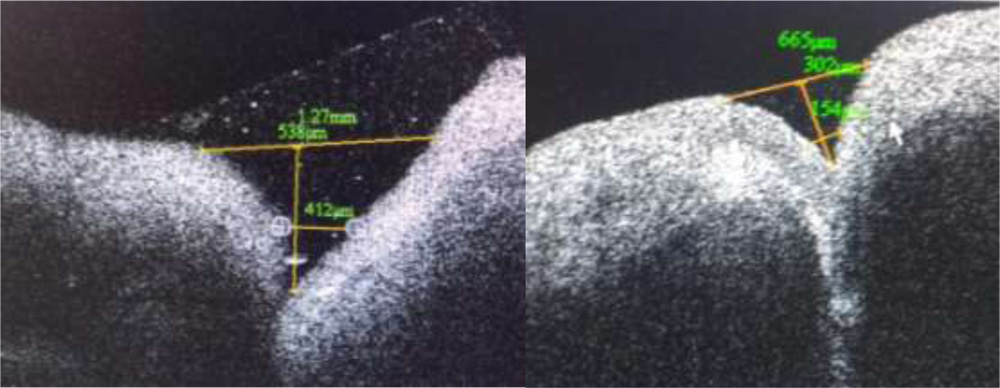

Punctalshape , contents, angulation of the medial and lateral wall was noted.Measurement of outer and inner punctal diameter and depth was done using adjustable distance measurement tool. A tangent drawn over the punctal opening towards lid margin was used to measure outer punctal diameter. Inner punctal diameter was measured with the help of a line drawn above the abrupt narrowing of inner lumen. A perpendicular was drawn from outer punctal diameter towards the base till the inner punctal diameter to measure the depth of the punctum.(Fig 2)

Fig 3 (e) Fig 3 (f)

Fig 3(a-f) Range of punctal morphological variation of shapes detected on SDOCT

This study recorded a mean outer punctal diameter of 700.1± 424.09 µ with a wide range of variation. The median value for outer punctal diameter was 584.5µ. This is more than previously recorded values of 214.7µ by Wawrwyznskyet al (2014), 247µ by Allam and Ahmad (2015) and 400.16 µ by Kamal et al7(2015). Timlinet al8recorded a mean outer punctal diameter of 646± 150 µ. All these values reflect a wide range of variation of punctal morphology, particularly punctal shape and depth. A saucer shaped punctum was found have a larger extent compared to a narrow v shaped punctum. A cross line method of scanning was used by Allam and Ahmed while linear scanning was done by Timlinet al and Kamal et al.

Mean inner punctal diameter was recorded as 245.5± 127.54µ at the level of narrowing and change in curvature of inner walls to a vertical from a horizontal one. A definite junction between lower end of punctum and vertical canaliculus could be identified as inner punctum. Inner punctal diameters were found to range from 101µ to 479µ. Allam and Ahmad recorded a mean inner punctal diameter to be 234± 139µ at a similar level. Timlinet al recorded a value of 50 ± 104µ at a depth of 500 µ from external punctum while inner punctal size was recorded as 125± 61µ mid way between punctum and visible lower end by Kamal et al.

The present study recorded mean punctual depth as 390.85± 229µ with a range of 132µ to 866µ. This is comparable to the mean punctal depth recorded by Allam and Ahmad et al as 252 ± 127µ In contrast Timlinet al recorded this value as 544± 327µ . Kamal et al recorded a depth of 890± 155µ. These two measurements represent the vertical canalicular depth as there is no identification of a separate inner punctum in all cases. Wawrzynskietal reported a mean depth of 753 ± 216 µ. This depth is representative of punctal and vertical canalicular depth. All studies report a depth of less than 2mm on imaging. It is difficult to identify the end point of vertical canaliculus and beginning of horizontal canaliculus by OCT imaging. Proximal lacrimal system has been easier to image and three dimensional reconstruction has been shown to be possible by Kamal et al.